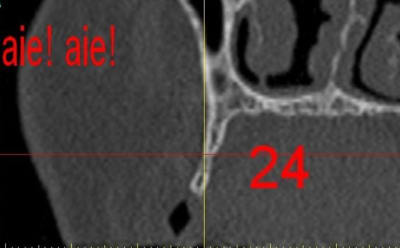

dar24_ocq9fn.jpg

La première diapo est un essai pour justifier le concept (os non destiné à une utilisation greffe)

la deuxième est "tapée" dans une tête de femur de mauvais qualité (rejetée)

la troisième et suivante ce sont "les greffons" définitifs.